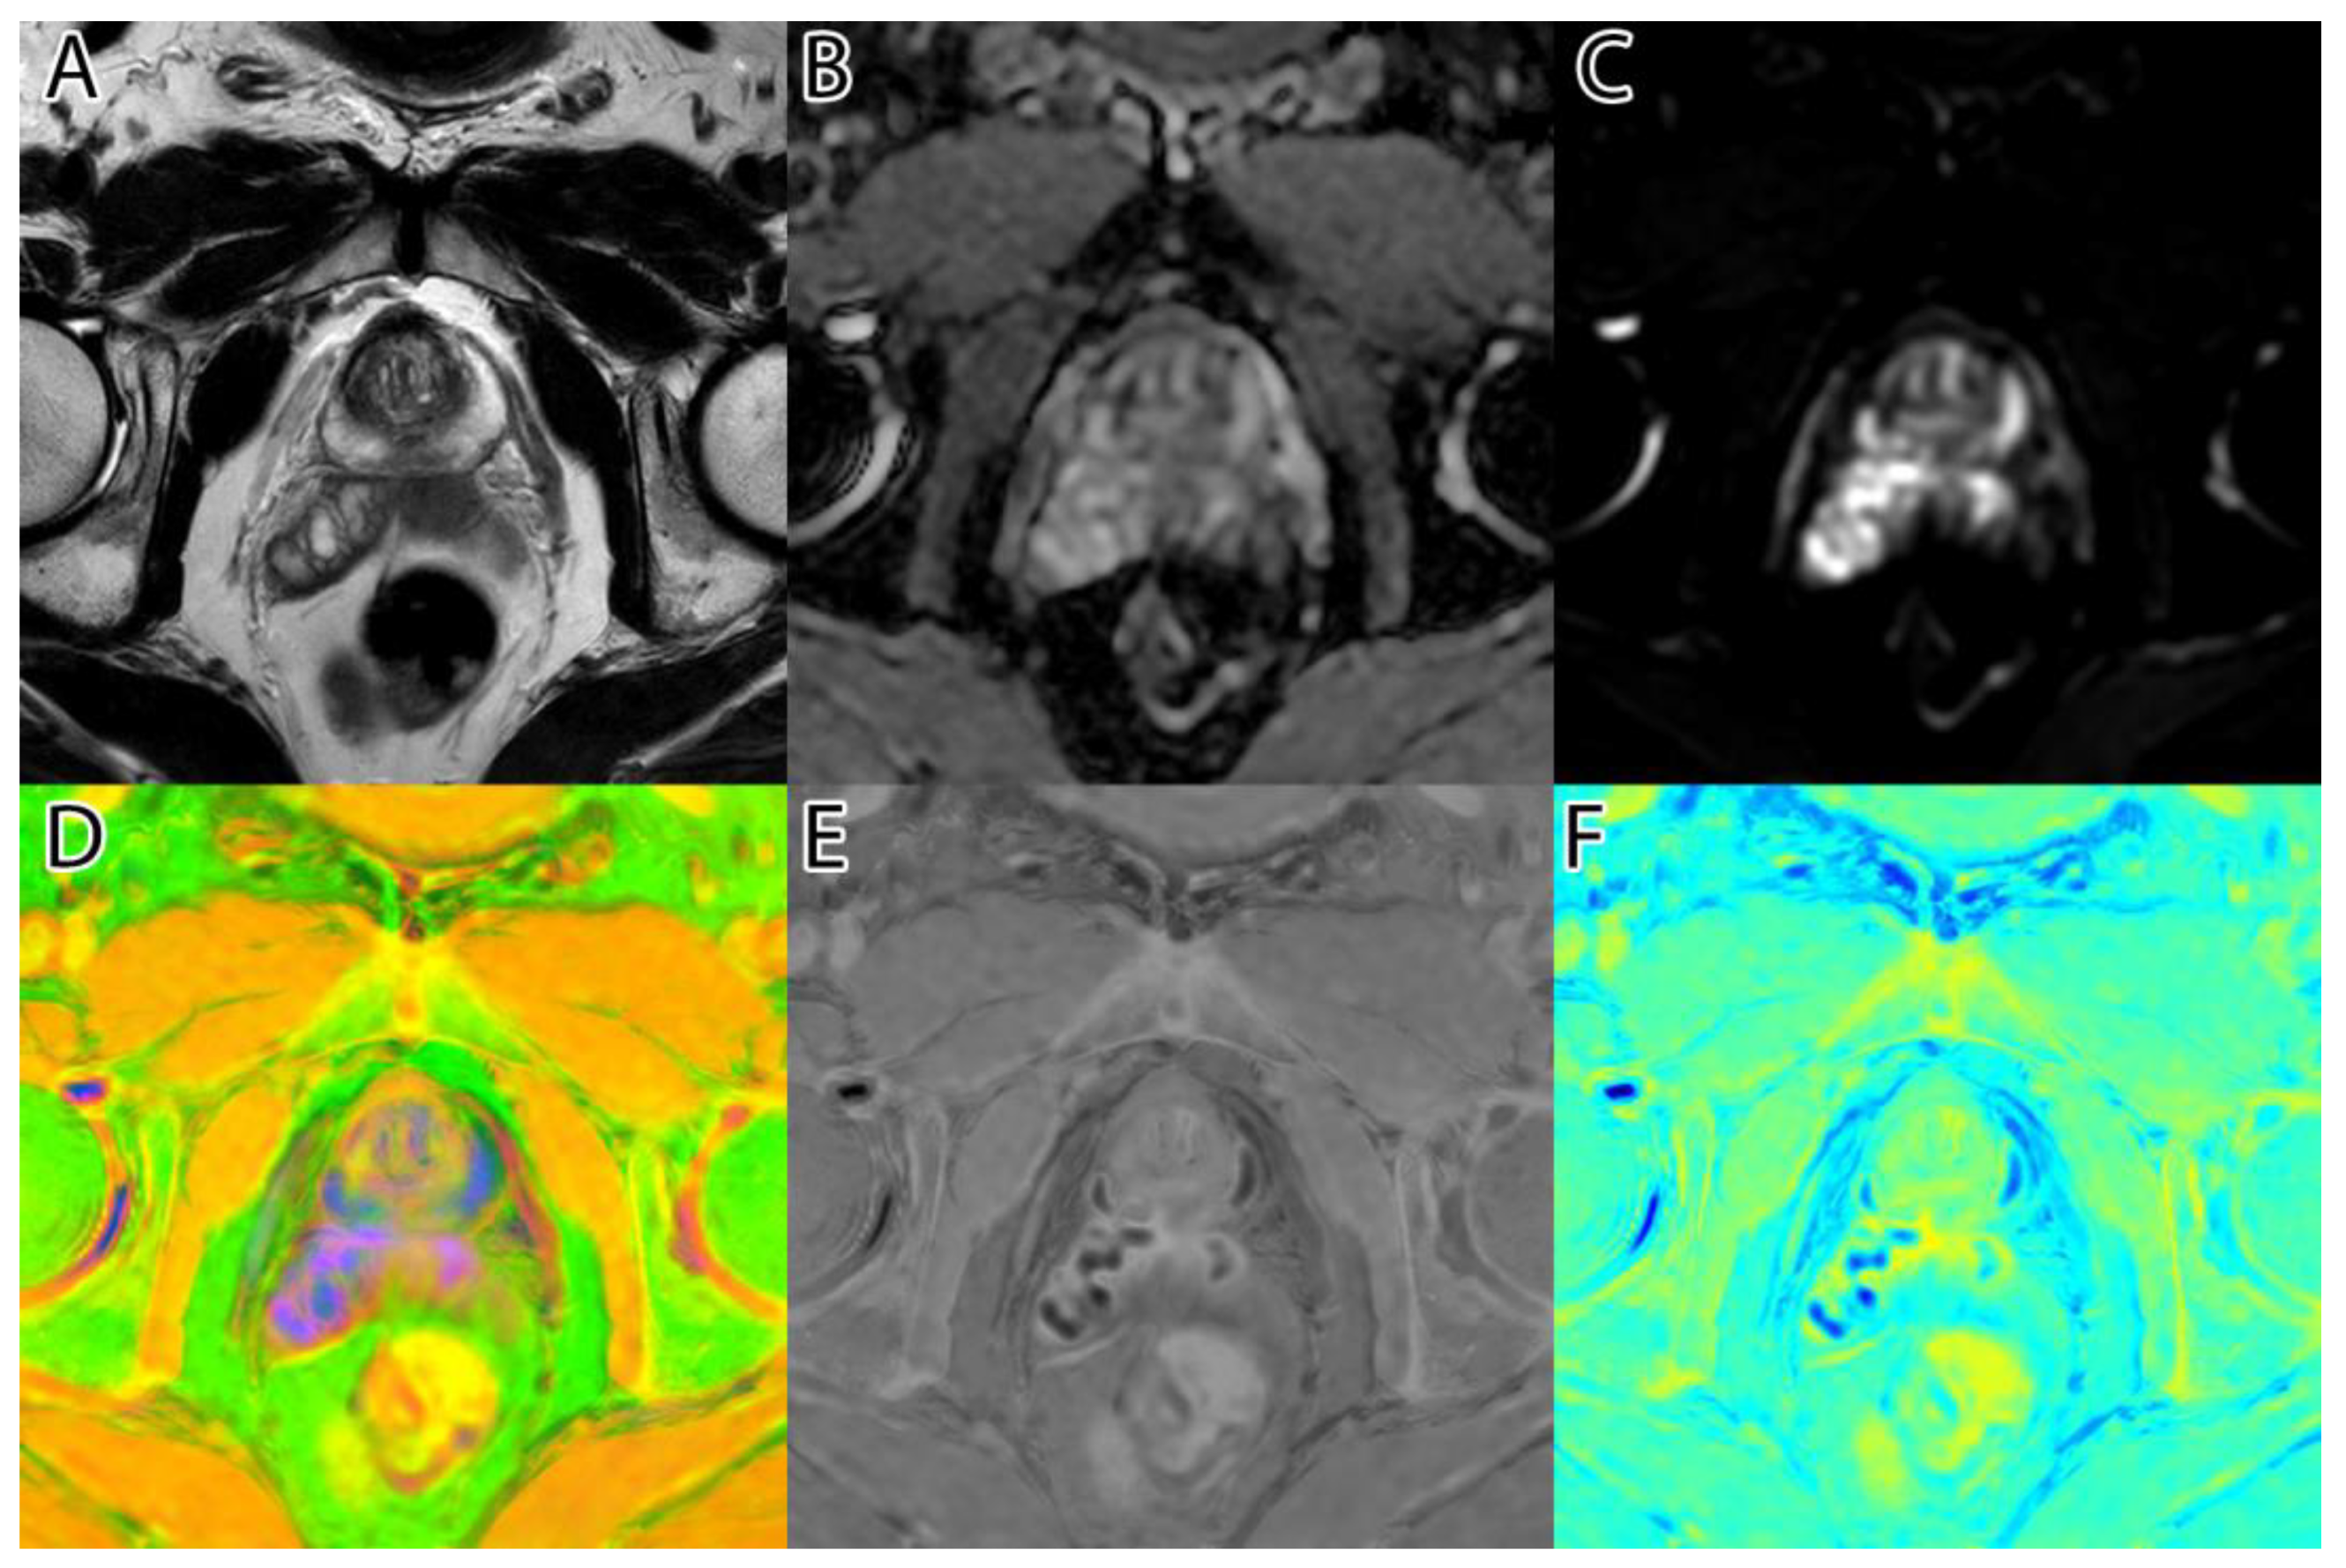

The second step was to compute the inversion of T2WI and ADC, thus obtaining the area of interest (tumor) represented by higher intensity values, as seen in Figure 1D,E. For this, we subtracted the actual image values from the maximum of 255.

Figure 1. Sample image: (A)—T2WI; (B)—ADC; (C)—DWI; (D)—inverted T2WI; (E)—inverted DWI; (F)—RGB images resulting from image fusion of (CE).

The third step was to combine the three images into an RGB (red, green, blue) image. T2WI was used for the red channel, ADC was used for the green, and DWI was used for the blue. The resulting image can be seen in Figure 1F.

The sixth and final step was to compute the final intensity mask by subtracting the square root from the square sum of the alpha–beta channels and subtracting the resulting value from the luminance. The resulting intensity image can be seen in Figure 2B and Figure 3B. By adding the ‘jet’ color map to it, we obtained a colored intensity map that highlights the tumoral areas, as seen in Figure 2C and Figure 3C.

Figure 2. PI-RADS 2 patient: (A)—T2WI; (B)—ADC; (C)—DWI; (D)—RGB fused image; (E)—grayscale tumor intensity image; (F)—‘jet’-mapped tumor intensity image.

Figure 3. PI-RADS 5 patient: (A)—T2WI; (B)—ADC; (C)—DWI; (D)—RGB fused image; (E)—grayscale tumor intensity image; (F)—‘jet’-mapped tumor intensity image.

The algorithm was used on all 204 images and computed the tumor intensity image. A sample from the original data, and the resulting fused image, can be seen in Figure 1.

Samples of the computed tumor intensity images can be seen in Figure 2 for a PI-RADS 2 patient and in Figure 3 for a PI-RADS 5 patient. Notice the difference in “jet” intensity between the control patient and the patient with extraprostatic invasion.